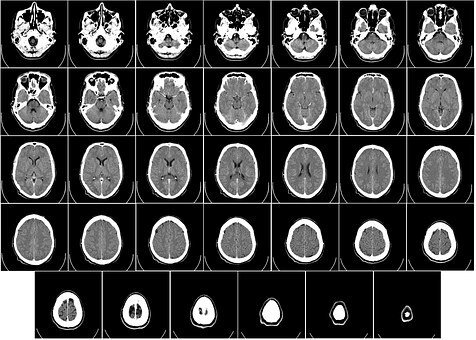

artwork I created out of my old med school anatomy book

The medical literature suggests that higher levels of Omega 3 fatty acids help protect the brain as we age. Published in Neurology, researchers found that higher omega-3 levels is neuroprotective, slowing the loss of brain volume that occurs as we get older.

For this study, researchers look at more than 1000 postmenopausal women using both blood samples and MRI imaging. ��They found that higher Omega 3 intake was associated with a higher total normal brain and hippocampus volume��� a measurement that was directly related to omega-3 fatty acid levels. ��Total brain volume was significantly smaller in the women with the lowest quartile of omega-3 index when compared with those in the highest quartile.

In addition, the hippocampus (the area of the brain specifically related to cognitive function) was protected as well��� found to be significantly smaller in the lowest vs the highest quartile of omega-3 levels. ��These results were statistical significant even after controlling for age, lipid levels, glucose, blood pressure, education level, and hormone therapy replacement.